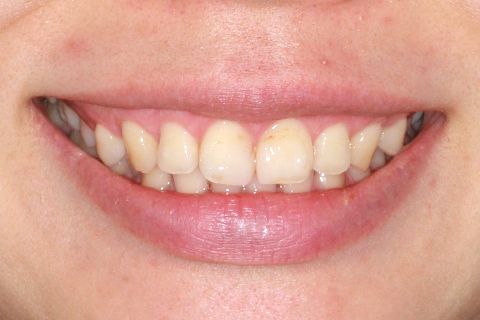

症例7(歯肉形成を併用した矯正治療)

治療後

歯肉形成(形成)症例7(歯肉形成を併用した矯正治療No.2)治療後

年齢・性別

16歳

治療期間

3年6ヶ月

抜歯

なし

治療費

80万円

治療内容

噛み合わせが深いのを改善するために前歯上歯肉に2本のスクリューを埋入して牽引。

施術の副作用(リスク)

疼痛、咬合時痛、知覚過敏、歯根吸収、歯肉退縮が生じる可能性があります。